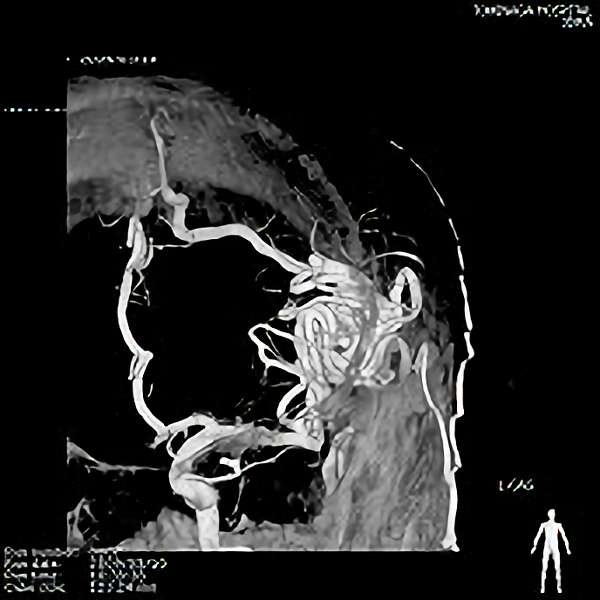

脳血管撮影

手術前

手術後